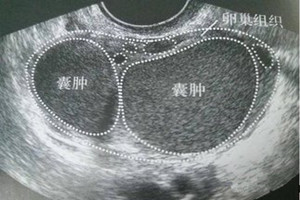

当然,还有一部分病人平时没有明显的不舒服,可能只是常规查体发现。除了妇科检查外,B超是最有价值的无创性检查方法,再联合一下血CA125检查,多数会明确诊断。还需要和其他类型的卵巢囊肿做鉴别,最最准确的是手术+病理诊断,其他的检查都可能存在一定的误差。